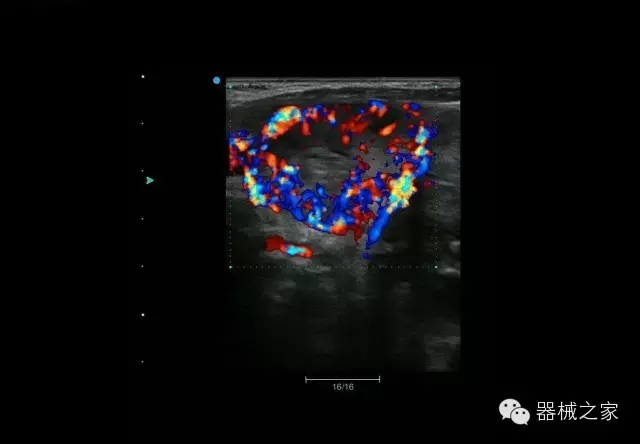

臨床圖片賞析

結(jié)甲

腎臟血流

肝血管瘤